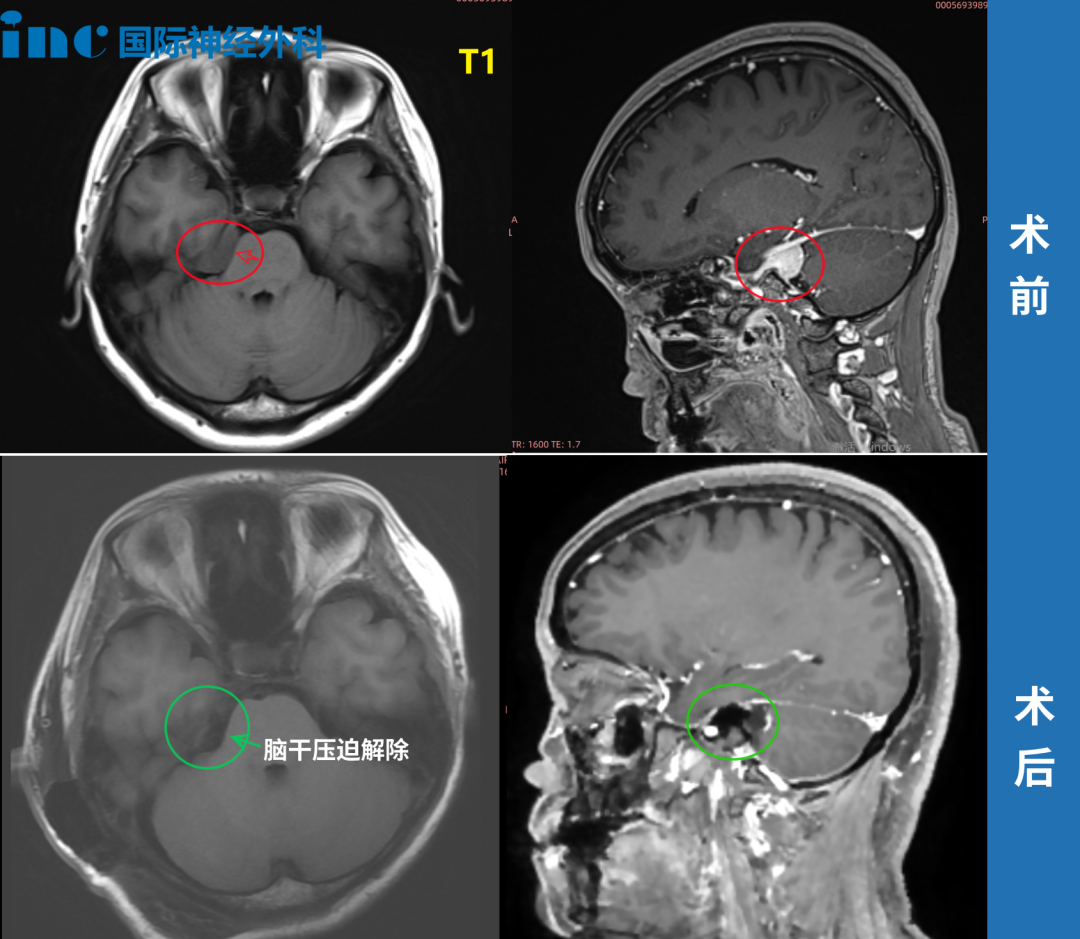

▼术前术后MRI对比

2022年,巴教授中国行中,巴教授成功主刀手术肿瘤全切,无新发神经功能损伤。

术后第一天ICU查房,钟女士状态清醒,和教授交流顺畅。术后第五天查房,钟女士状态良好,连声感谢巴教授并和教授开心合影。病理结果脑膜瘤WHOI级,良性预后很好,术后将不再需要反复放化疗,她可以像正常人一样生活。术后2年,复查核磁无复发。